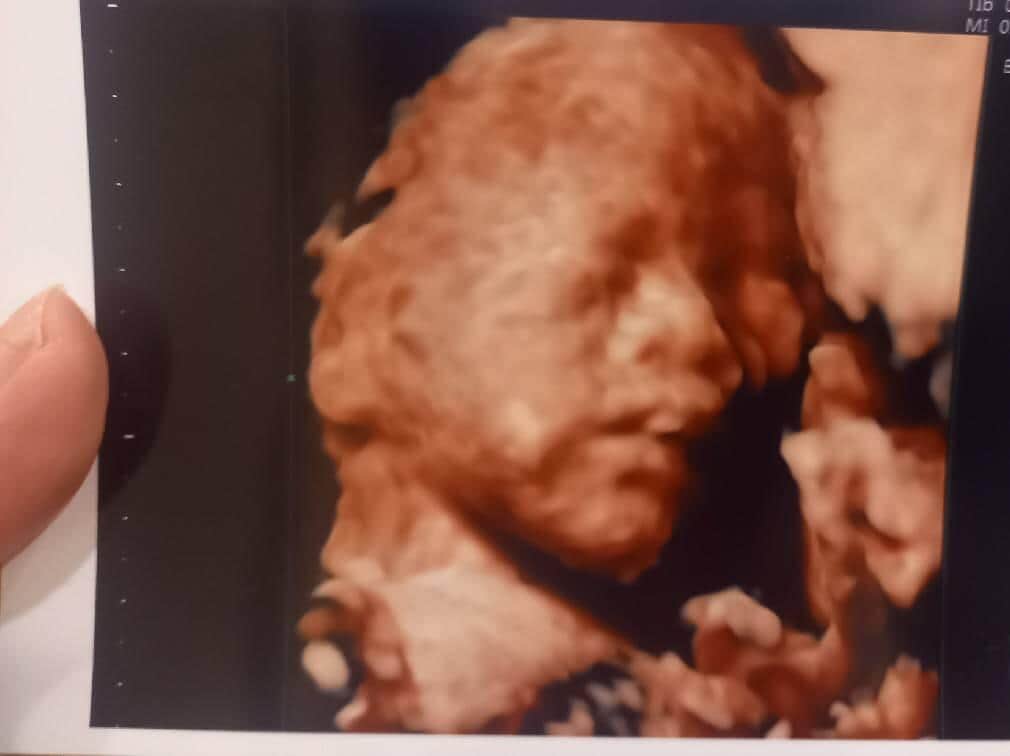

4Dエコー。赤ちゃんの顔がハッキリしてきた!